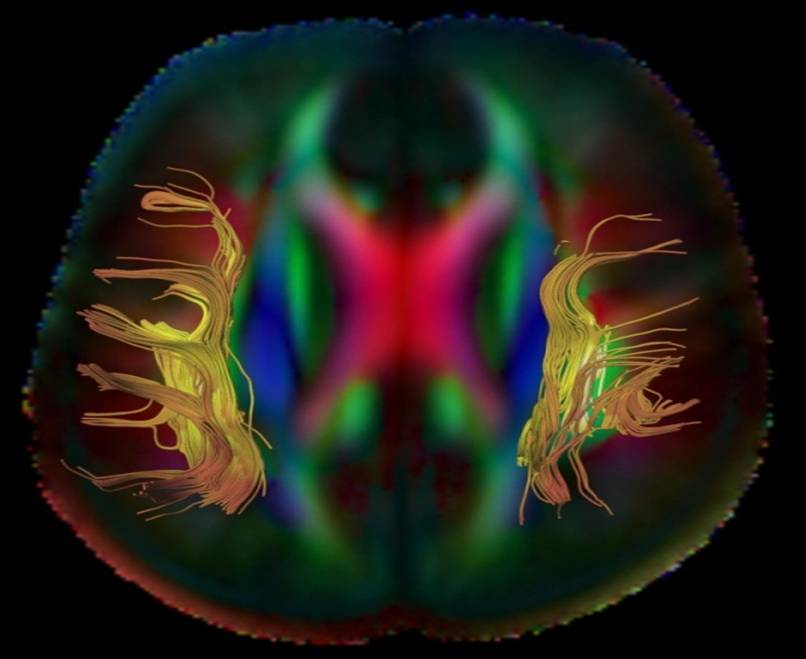

Diffusion Tensor Imaging (DTI)

Diffusion Tensor Imaging (DTI) is a way of using measures of water diffusion to reflect the integrity of white matter tracts and structural connectivity in the brain.